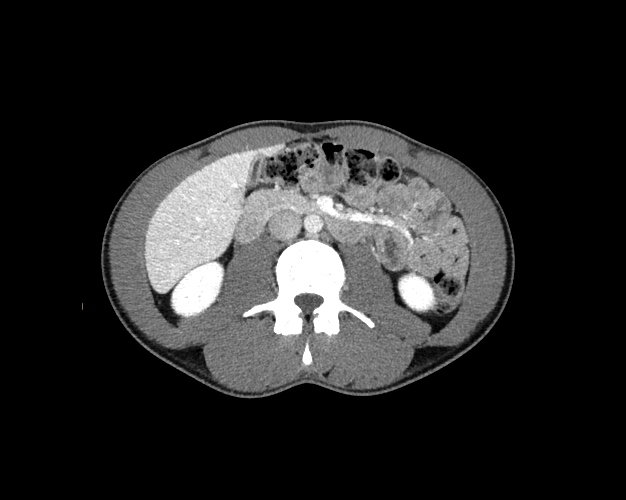

Body

Covers abdominal CT anatomy.